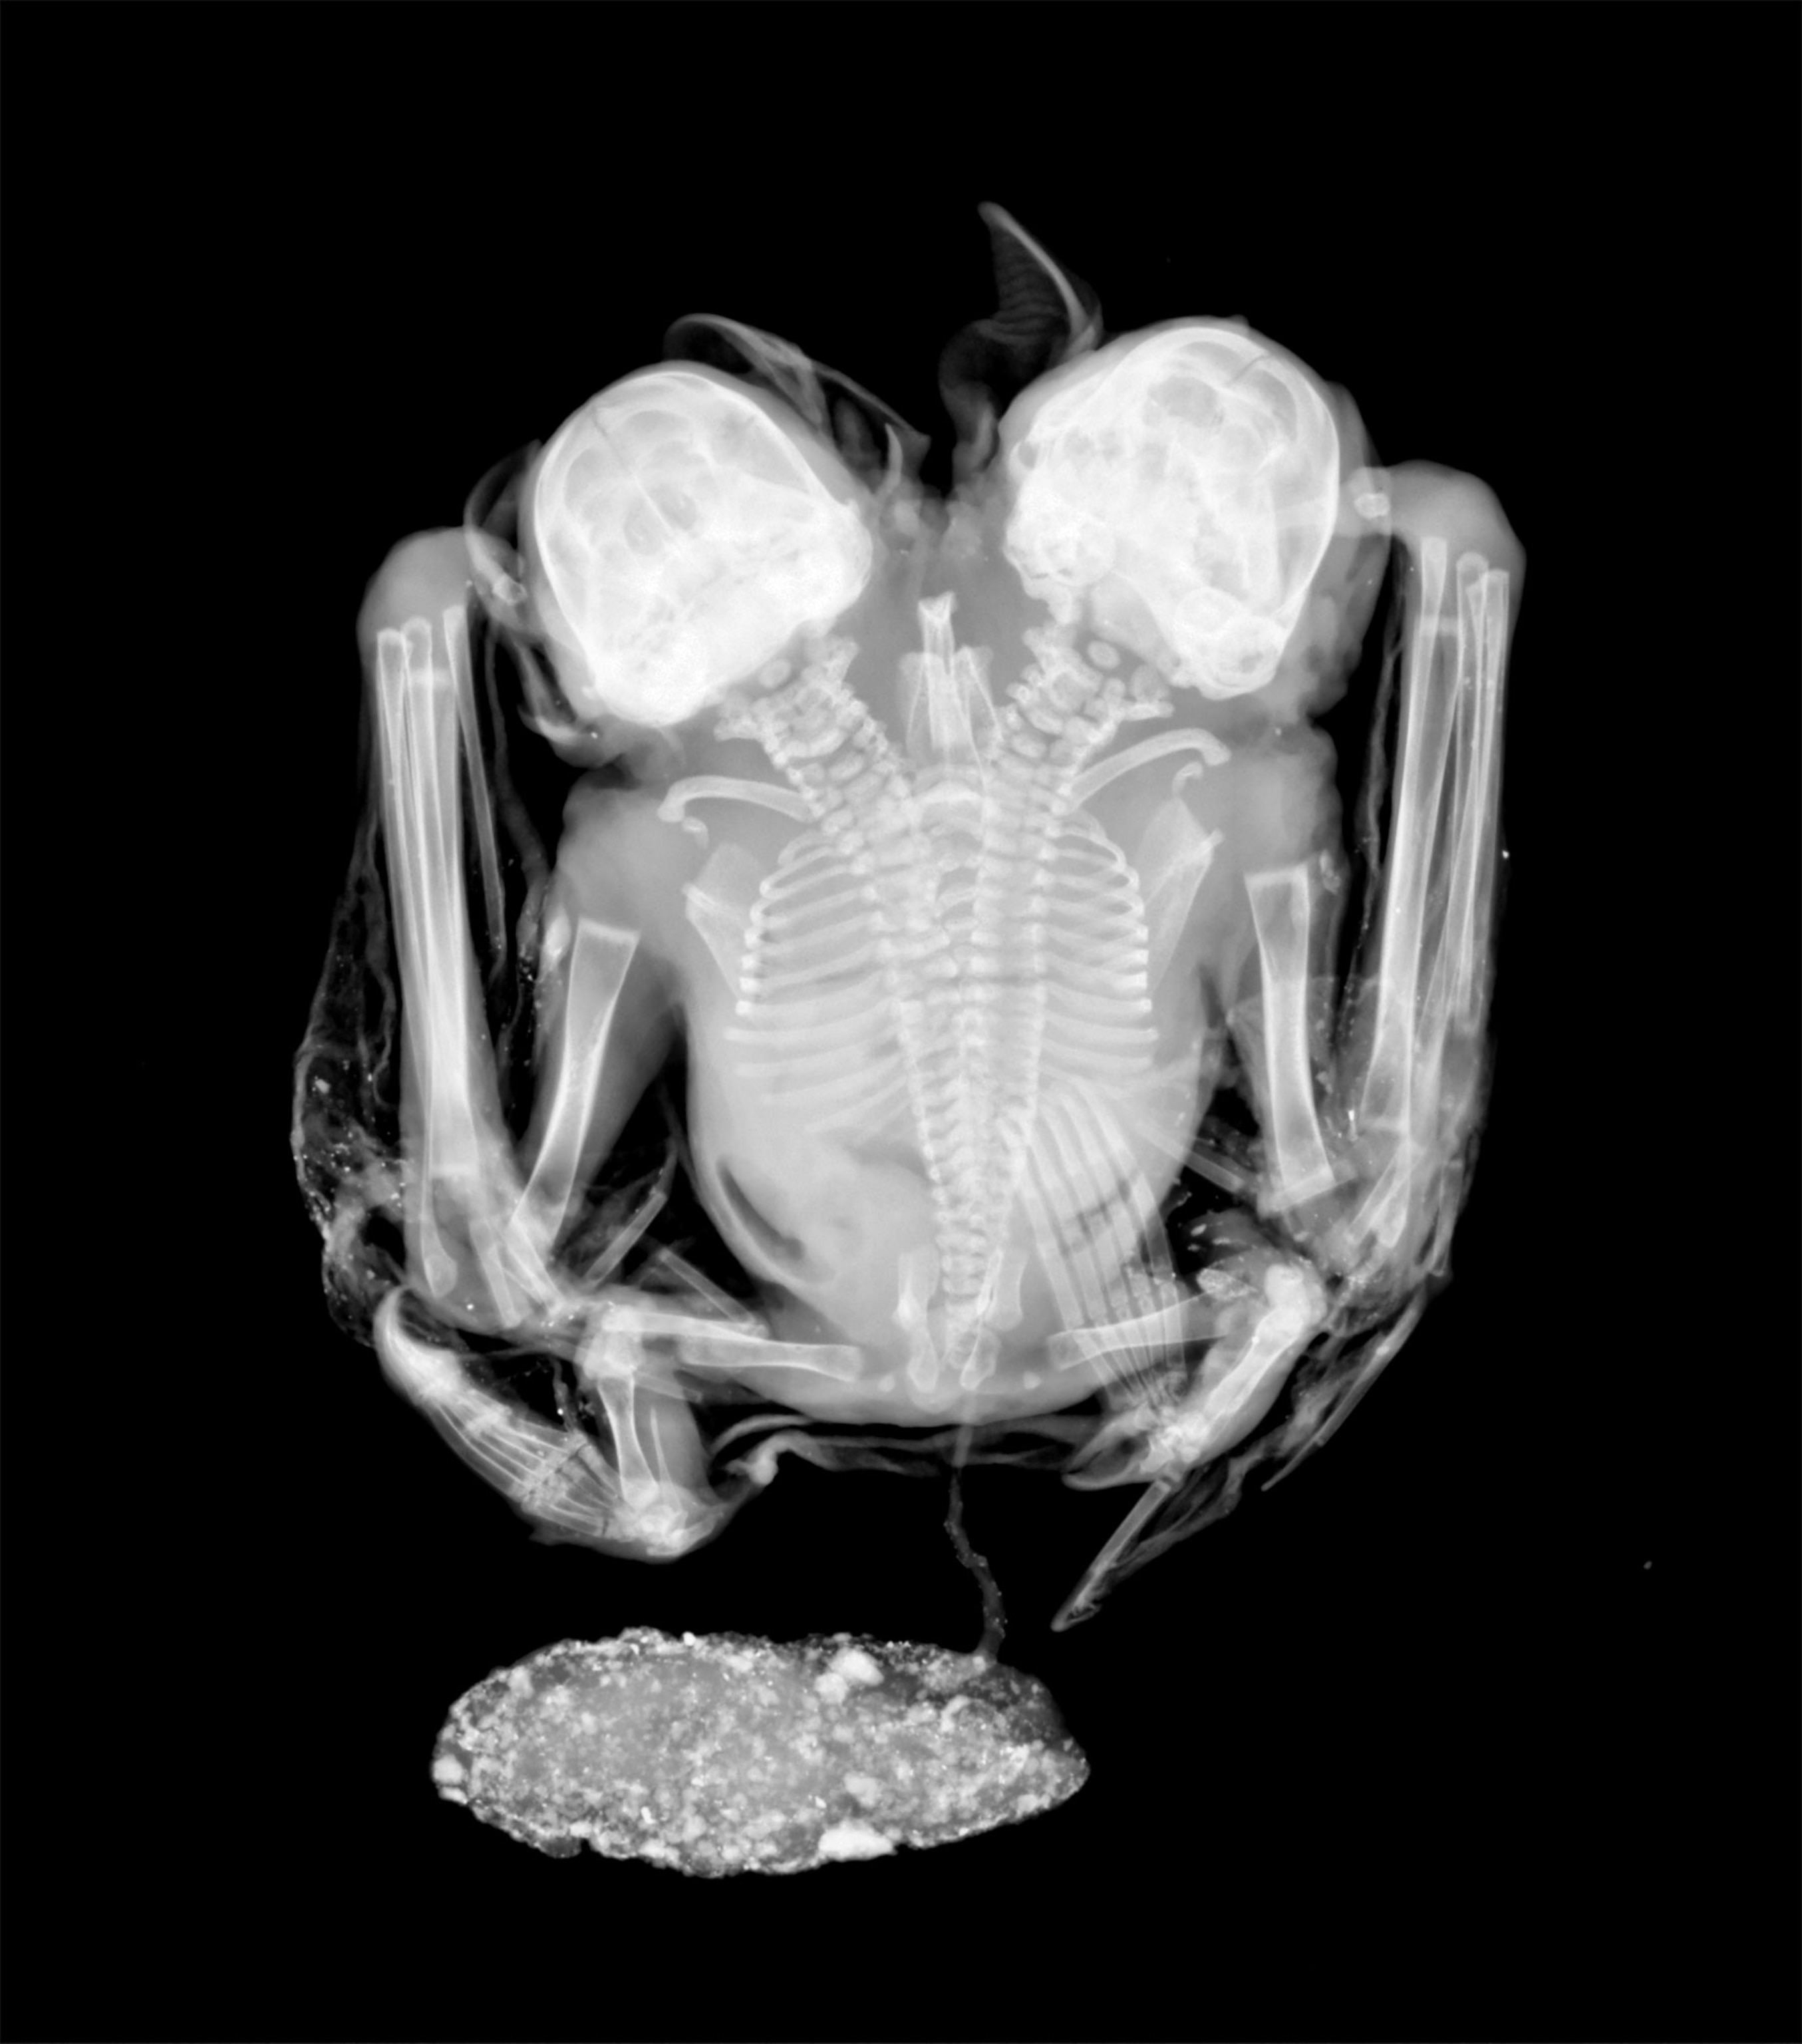

An x-ray shows these male bats have separate heads and necks, but their spines eventually converge. They also have two similarly sized but separate hearts. (See a rare two-headed porpoise.)

The researchers believe these bats are newborn Artibeus bats from their physical characteristics, and also surmise they died at birth or were stillborn as their placenta is still attached.